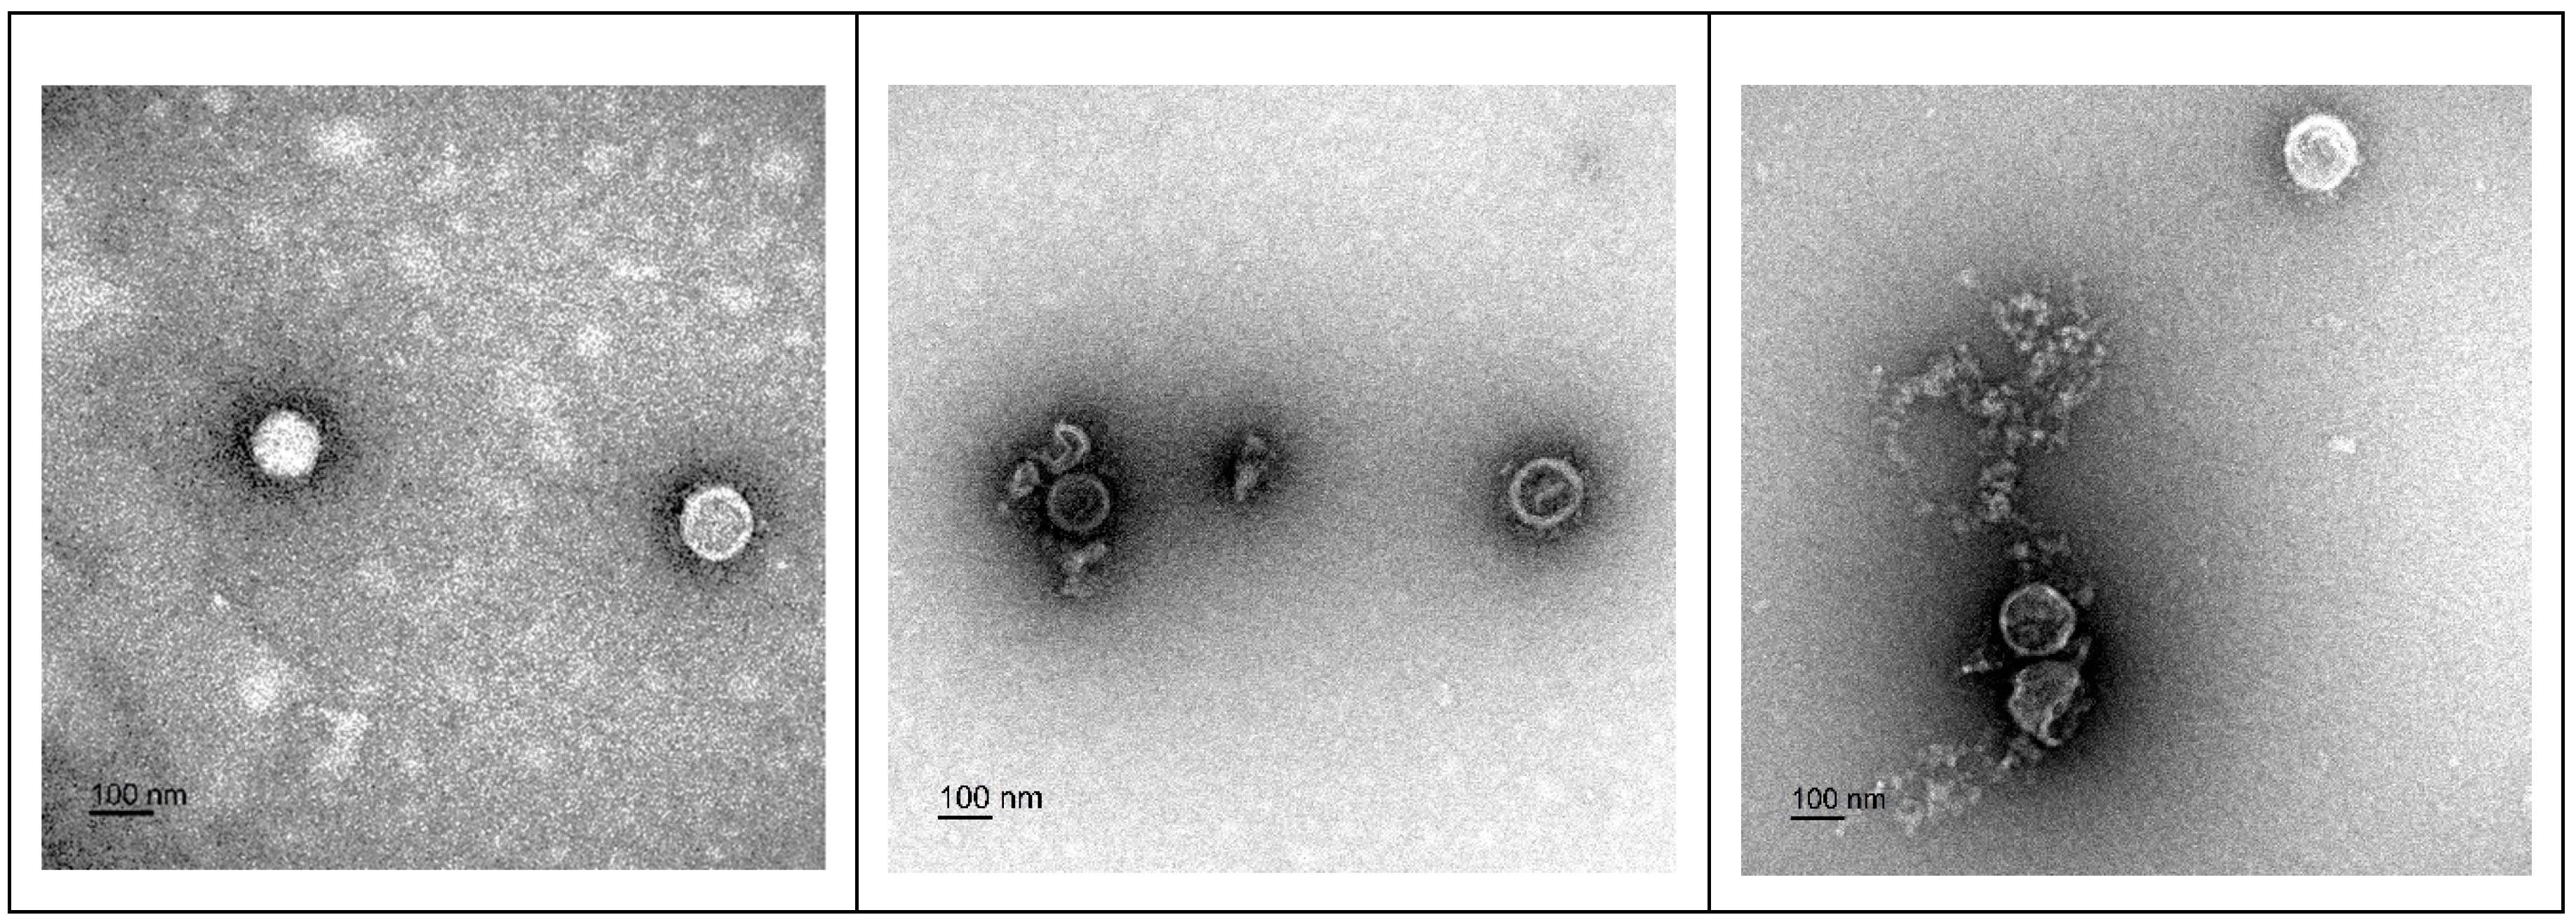

3.3. Transmission Electron Microscopy (TEM) Imaging of F18D-Treated Virus